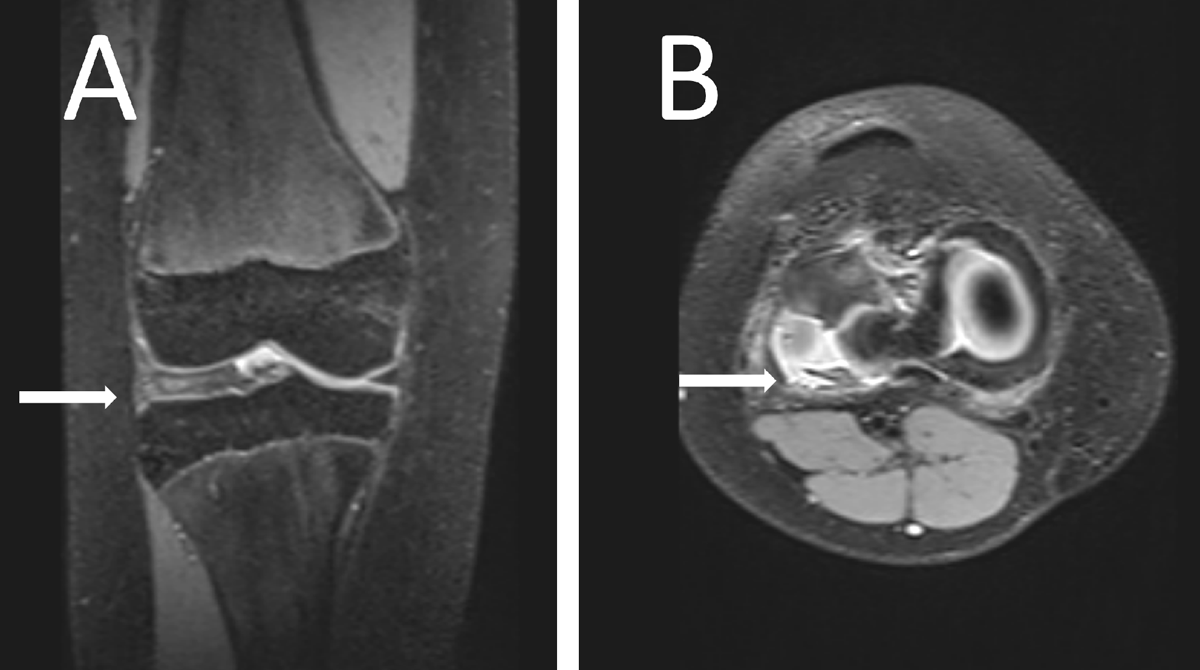

Figure 1

Proton density fat-saturated image of the girl’s knee showing a lateral discoid meniscus (arrow) in a coronal plane (A) and a degenerative, disinserted, meniscus with an anterior subluxation and posterior residual meniscal fragment facing the popliteal hiatus (arrow) in an axial plane (B).